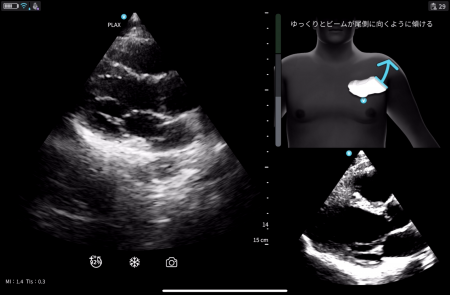

※Cardiac Guidance/ Interpretationの実際の画面

1. Cardiac Guidance

リアルタイムで操作者をサポートするガイド機能で、プローブ(探触子)の位置、角度、肋間操作、深度を画面上で指示し、より正確で高品質な画像取得をサポートします。さらに、画像品質のインジケータ機能を備えており、最適なスキャン画像が得られているか否かを判定します。また、一定レベル以上の品質を認識した際には、プローブを一定時間保持することで自動的に画像を保存します。Cardiac Guidanceの機能により、複雑な心エコー検査を簡便かつ正確に実施することが可能となり、臨床現場だけでなく、大学や基幹病院のトレーニングセンターでの教育利用にも「Vscan Air SL Ally」の導入が期待されます。

※Cardiac Guidanceによる心エコー検査のリアルタイムガイド表示機能。Quality Meterで画像クオリティを確認、画面上部にはイラストとともに「時計回りにゆっくりと回転」などリアルタイムに様々なガイダンスが表示されます。